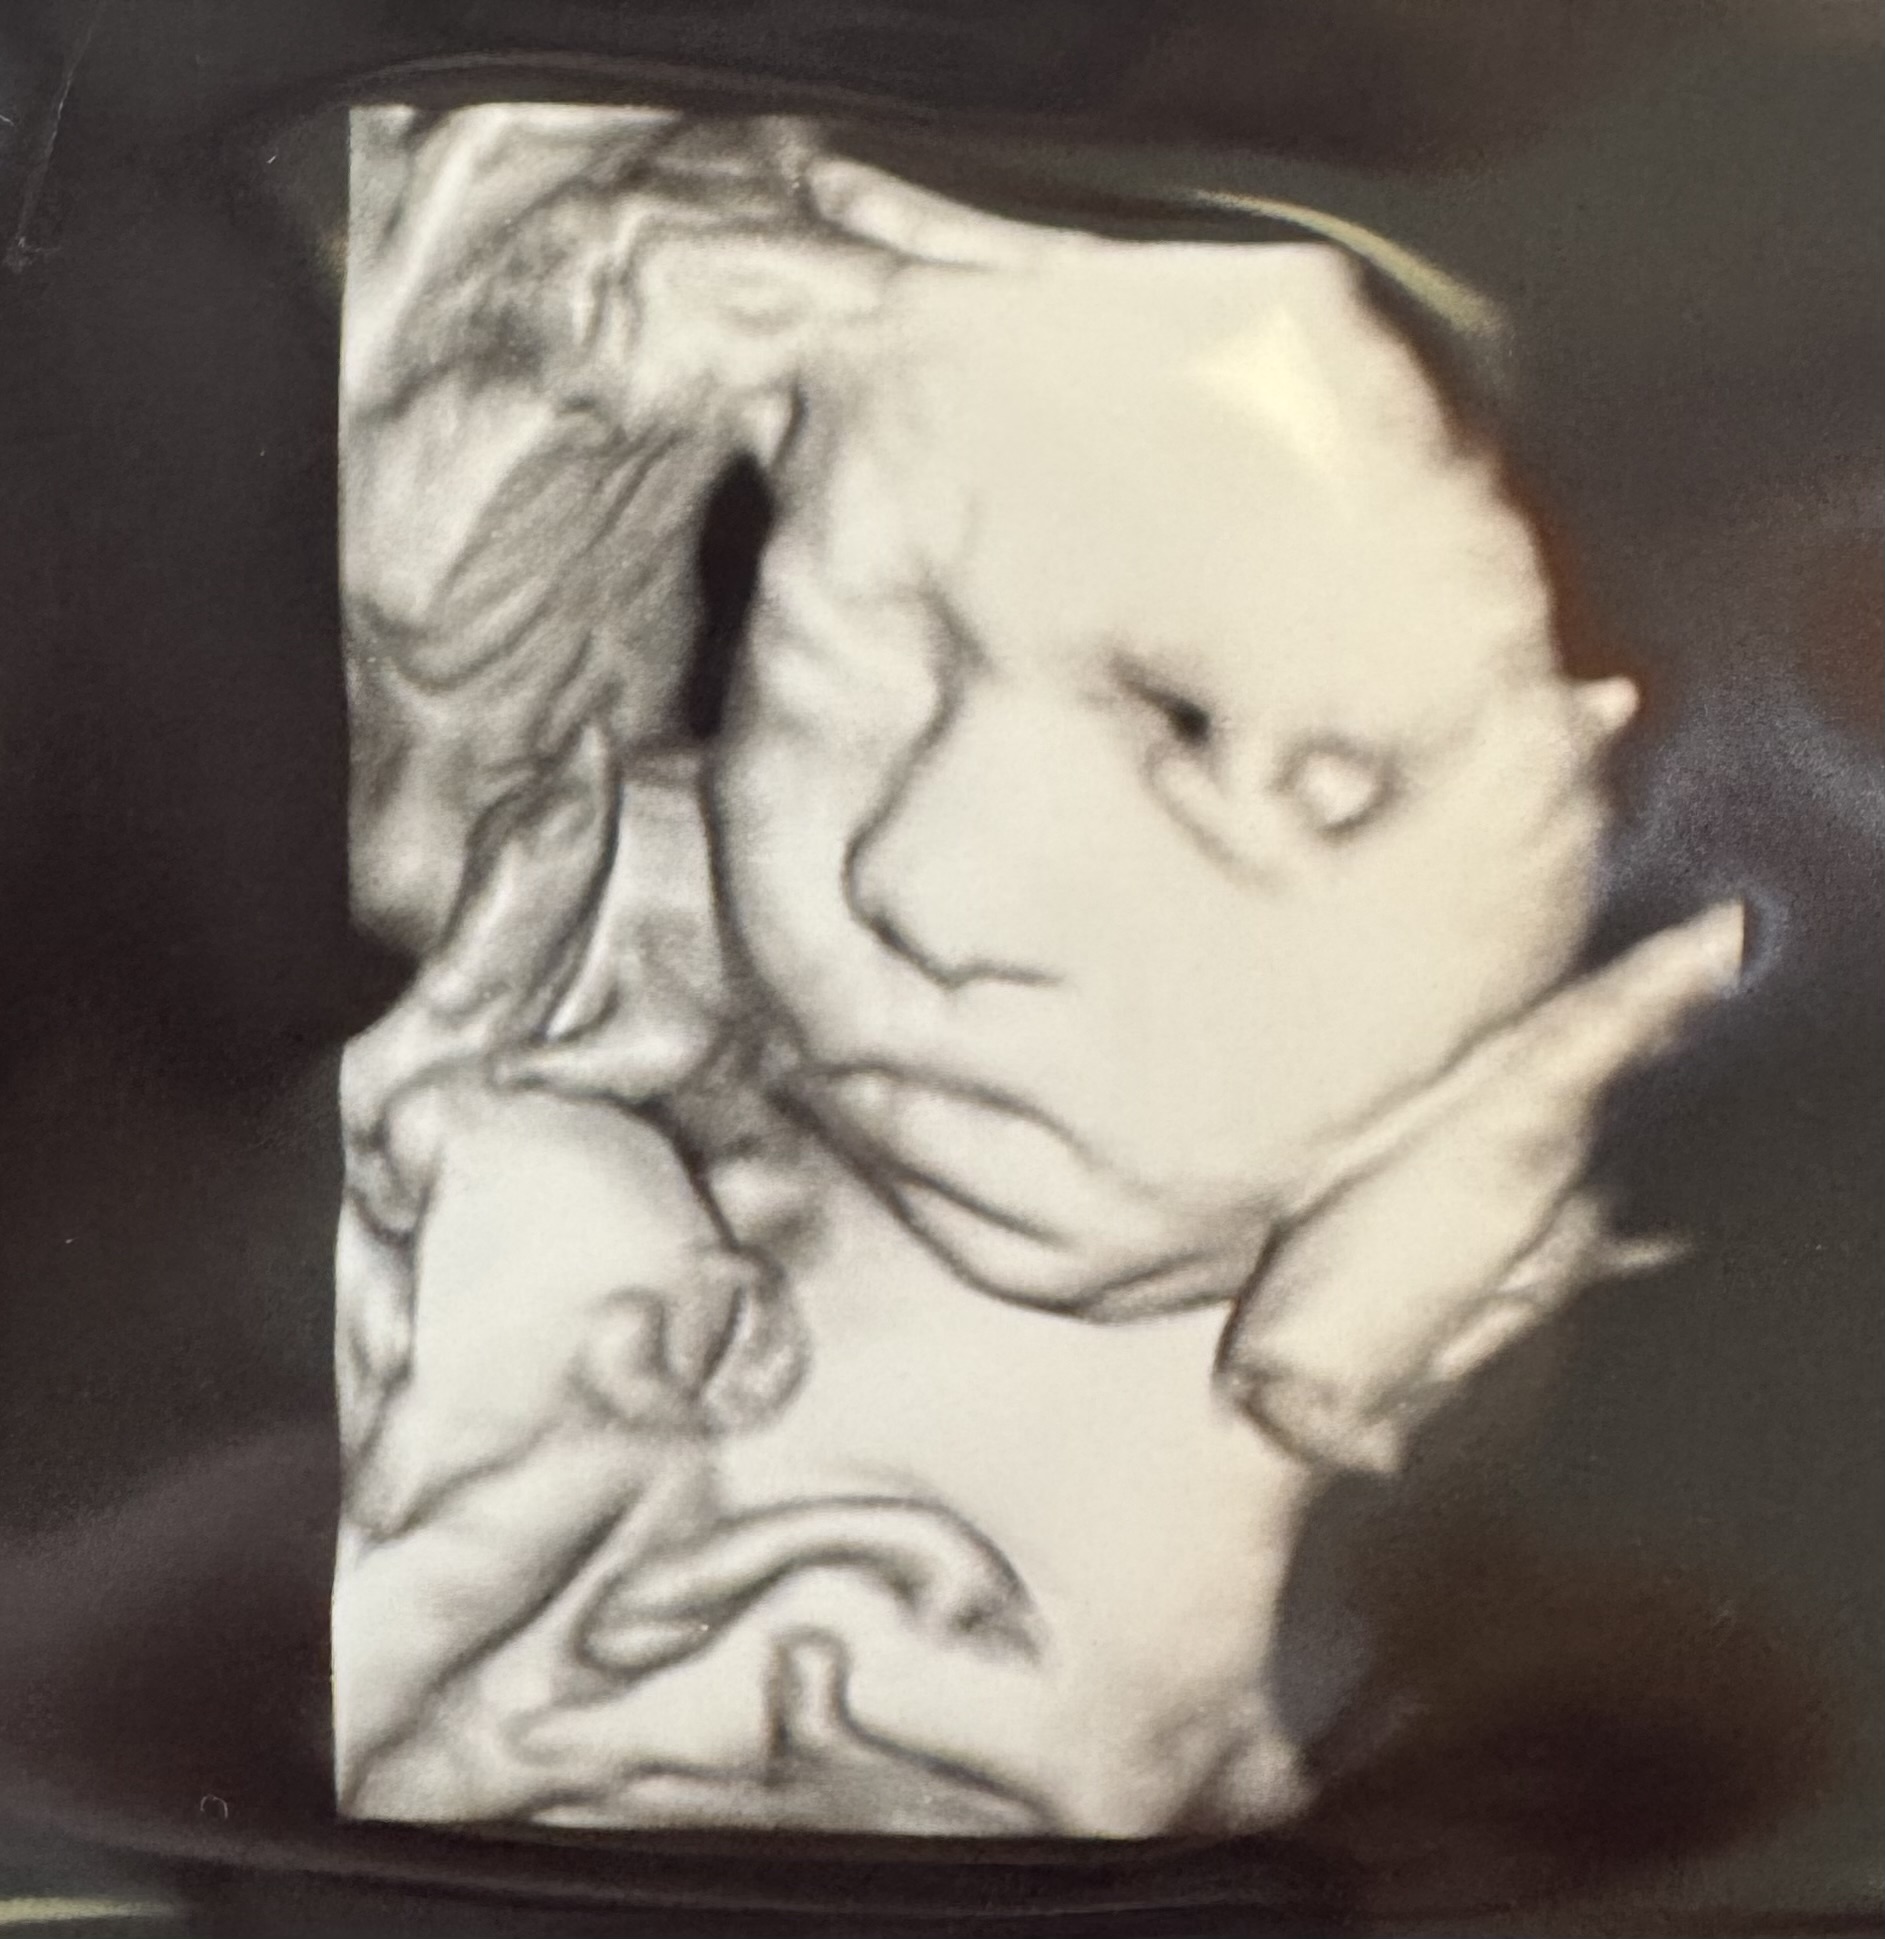

My po 3 prenatalnych, więc się melduję- 1290 gram niuni, ułożona główkowo 🫶🏻 bardzo ładnie zapozowala, pierwsze co lekarz zrobił to foteczka 😂 i słusznie, bo potem pokazała co potrafi. Doktor powiedział że dobra akrobatka rośnie i że bardzo ruchliwym jest dzidziusiem 😅 wszystko w porządku ❤️

https://zapodaj.net/plik-Cj6tI6Xv1m